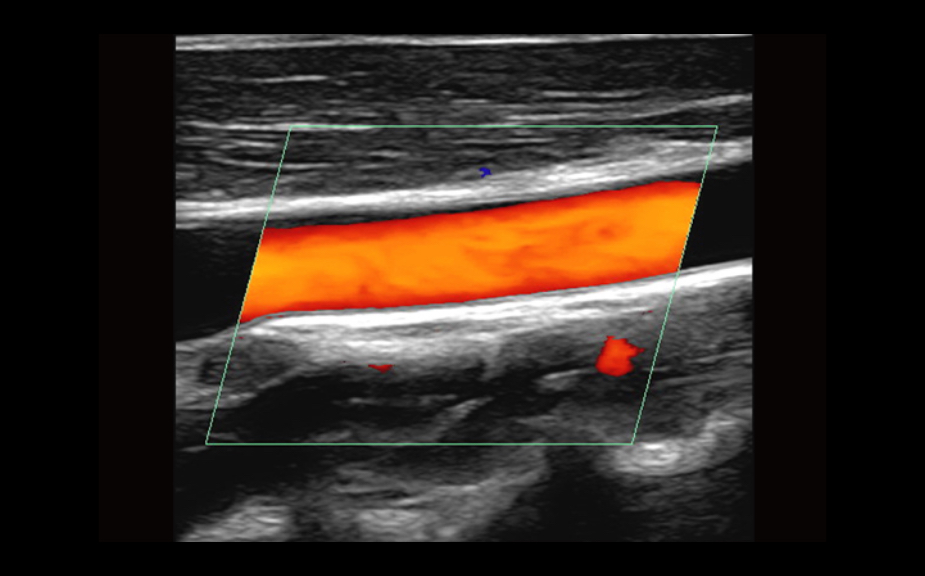

Equipped with patented, software based ZONE Sonography? Technology (ZST), the Z.One PRO provides optimally detailed B-mode and Doppler imaging for patients, regardless of body habitus, helping assure a reliable diagnosis.

Throughout a wide range of applications, the Z.One PRO is the ultrasound solution for your demanding clinical challenges.

- Unsurpassed image quality across all applications

The Z.One PRO is powered by ZONE Sonography Technology, an innovative and proprietary image formation architecture that acquires and processes acoustic data up to ten times faster than conventional beamforming methods.